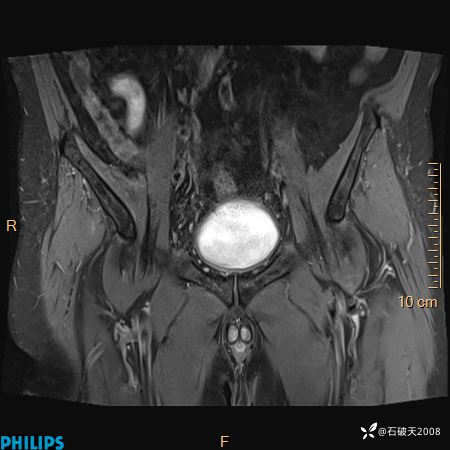

2023年3月份MRI影像

T2压脂冠状位